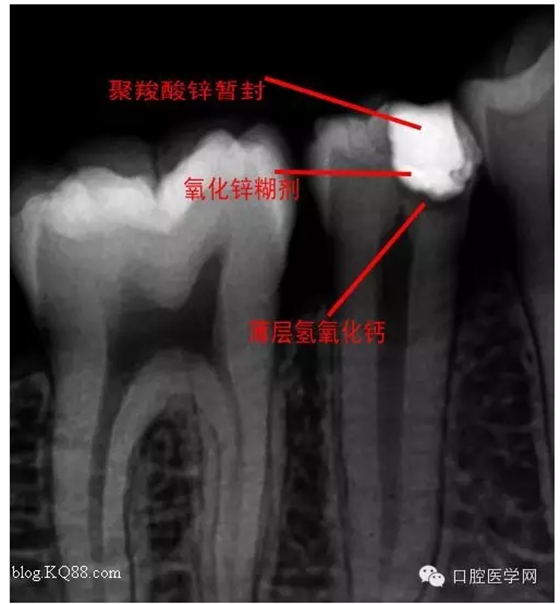

去腐,備洞。發(fā)現(xiàn)已經(jīng)露髓。根據(jù)年輕恒牙保存活髓治療原則。選擇直接蓋髓術(shù)?;颊呤俏业闹种辣4婊钏璧闹匾裕灾皇亲隽撕?jiǎn)單的溝通。如果其他病人遇到這種情況術(shù)前溝通很重要。首先灌輸保髓的重要性,告知術(shù)后反應(yīng),以避免不必要的麻煩

術(shù)后第二天問(wèn)小伙:什么反應(yīng)?答:輕微脹痛,無(wú)冷熱痛,無(wú)咬合痛。我驚愕因?yàn)榛卮鸬膲驅(qū)I(yè)。不愧是金牌助手。呵呵,如果病人這樣回答您會(huì)???在啰唆幾句:操作中無(wú)菌是關(guān)鍵。從露髓的一刻起就不應(yīng)與唾液接觸。去腐后生理鹽水沖洗窩洞,但不要加壓或生理鹽水棉球輕輕擦拭窩洞。柔風(fēng)吹干